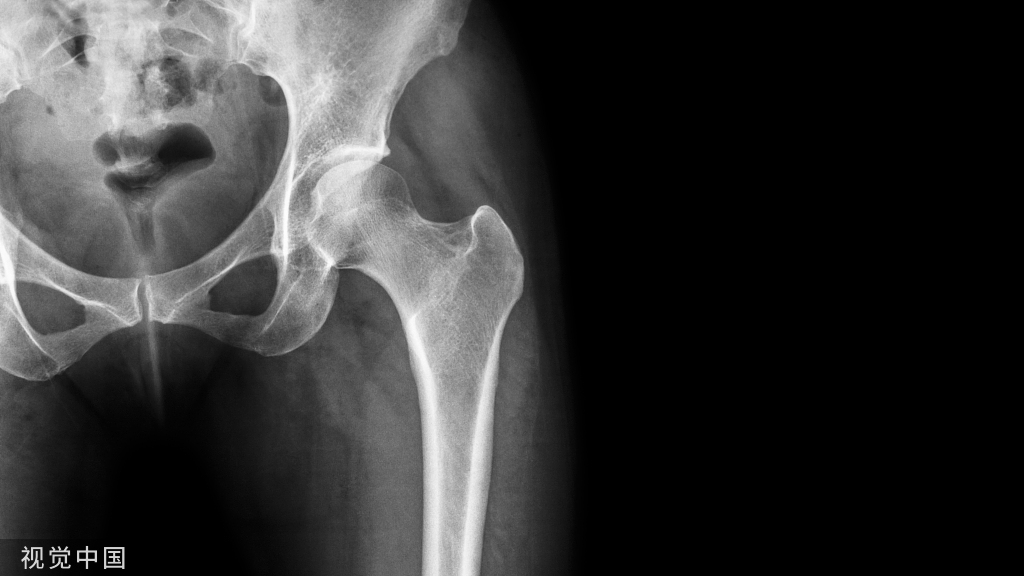

带锁髓内钉的应用扩大了髓内钉的手术指征,目前使用最多的是各种扩髓带锁髓内钉系统,主要用于髋部骨折(股骨转子间、转子下骨折)、股骨于骨折、股骨远端骨折、胫骨干骨折、肱骨骨折(外科颈骨折、肱骨干骨折)。

闭合骨折髓内钉使用的适应症和禁忌症:1)股骨:适应症有较远端的股骨髁上骨折到转子下,转子间的各种类型股骨骨折,包括螺旋骨折、节段性骨折、严重粉碎性骨折、所有纵轴稳定性不满意的骨折几乎均为髓内钉的适应证,同时并发同侧股骨颈和股骨干骨折、位于股骨转子下和股骨髁上之间的股骨假关节。禁忌症主要是粉碎股骨颈和转子间骨折不能很好固定时、老年骨质疏松患者无法适当固定时。

4.4股骨近端髓内钉

股骨近端髓内钉系统( proximal femoral nail system,PFN)是由AO内固定学会根据 Gamma钉原理改良设计而研制的用于股骨近端骨折治疗的髓内固定材料。PFN 适用于股骨颈基底至小转子以下 5cm 的骨折,也就是 AO 分类中 31-A的所有骨折和转子高位股骨干骨折。